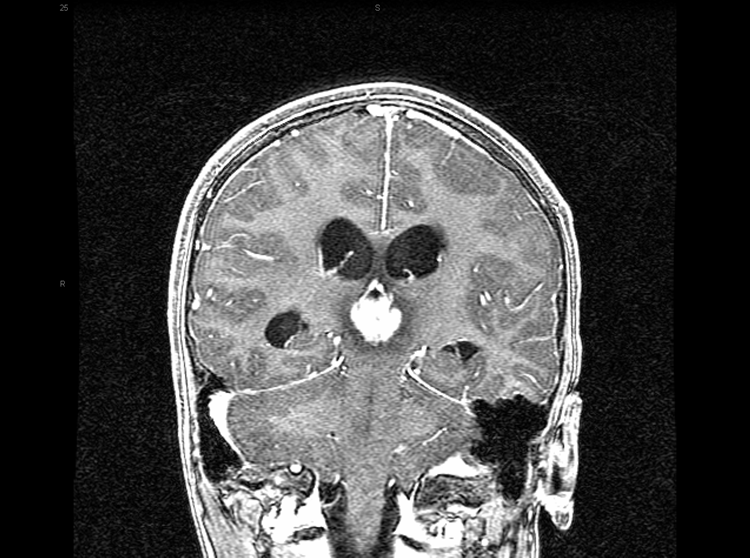

这名8岁的男孩,有肥胖和鼻窦炎的病史,在1天内出现急性神经功能衰退。他一直处于他的正常健康状态,直到报告的早上,当他抱怨新出现的头痛,恶心...